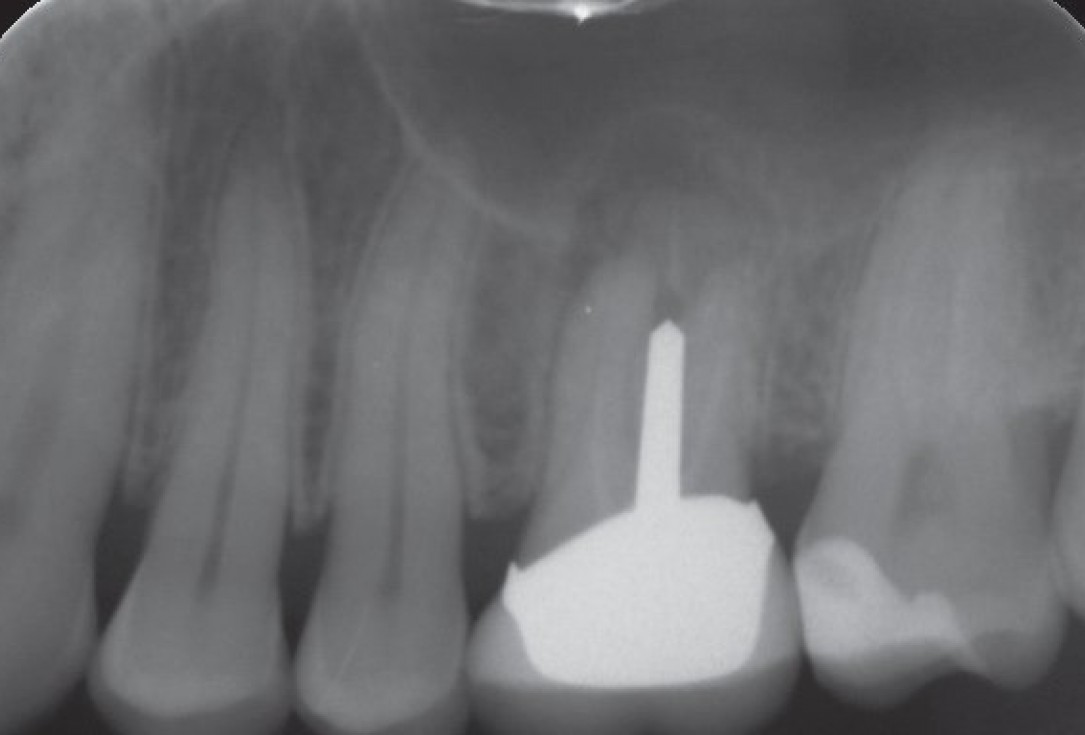

01/10 - Endodontically treated tooth 26 with apical cyst formationInternal sinus lift with maxresorb® inject - case Dr. Frank Kistler

02/10 - X-ray control before implantation with partially regenerated extraction socketInternal sinus lift with maxresorb® inject - case Dr. Frank Kistler